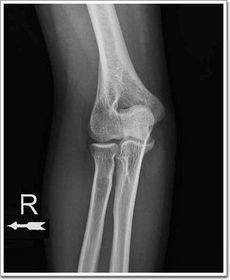

| AP Elbow | humerus is externally rotated because the epicondyles are not in profile |

| AP Oblique Elbow Internal Rotation | Insufficient obliquity |

| AP Oblique Elbow Internal Rotation | Excessive obliquity |

| AP Oblique Elbow External Rotation | forearm is not parallel to IR capitulum-radial joint is closed olecranon is not in the fossa |

| AP Oblique Elbow External Rotation | Underrotation distal forearm slightly elevated |

| AP Oblique Elbow External Rotation | Overrotation |

| Lateral Elbow | The elbow is elevated above the level of the shoulder radial head anterior to coronoid - should be superimposed capitulum too proximal to trochlea radial tuberosity seen - hand is pronated |

| Lateral Elbow | Elbow is depressed below the level of the shoulder radial head superimposed by coronoid capitulum too distal to medial trochlea |

| Lateral Elbow | the distal wrist is elevated hand is pronated because you can see the radial tuberosity - should not see that |

| AP Elbow | ANATOMY: distal humerus - proximal forearm CRITERIA: slight superimposition of proximal radius/ulna humeral epicondyles in profile open joint space POSITIONING: CR perpendicular @ midelbow |

| Medial Oblique Elbow | ANATOMY: proximal radius/ulna, distal humerus, medial epicondyle and trochlea CRITERIA: coronoid process in profile radial head and neck should superimpose the ulna olecranon process seen within olecranon fossa POSITIONING: CR perpendicular @ midelbow |

| Lateral Oblique Elbow | ANATOMY: open joint space, radial head, neck, tuberosity, and capitulum CRITERIA: radial head, neck, and tuberosity are free of superimposition humeral epicondyles and capitulum in profile POSITIONING: CR perpendicular @ midelbow |

| Lateral Elbow Evaluation Criteria | ANATOMY: distal humerus, proximal forearm, entire elbow joint CRITERIA: humeral epicondyles are superimposed radial tuberosity is invisible (if visible the hand is pronated) half of the radial head superimposed by coronoid process Elbow is flexed 90 degrees to see/not see fad pads 3 concentric arcs visible POSITIONING: CR perpendicular @ lateral epicondyle |